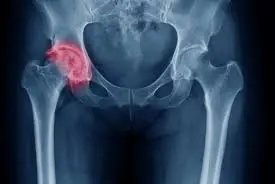

خشونة مفصل الحوض هي حالة تنكسية تؤثر على مفصل الورك الذي يربط بين عظمة الفخذ وعظمة الحوض، ويحدث ذلك عندما يتآكل الغضروف الذي يغطي نهايات العظام داخل المفصل، مما يؤدي إلى احتكاك العظام ببعضها البعض. هذا الاحتكاك يسبب الالتهاب، الألم، والتصلب، وغالباً ما يزداد سوءاً مع التقدم في العمر.

إذا لاحظت اعراض خشونة مفصل الحوض، ينصح بزيارة الطبيب فوراً لتشخيص دقيق عبر الأشعة السينية أو الرنين المغناطيسي، حيث يمكن أن تكون هذه الأعراض مؤشراً على بداية درجات خشونة مفصل الحوض المبكرة.

- الدرجة 2 (معتدلة): تضيق المساحة المفصلية، ظهور نتوءات عظمية (osteophytes)، ألم أكثر وضوحاً.

- الدرجة 3 (متوسطة إلى شديدة): تآكل واضح، تضيق كبير، تورم، وتقييد حركي.

- الدرجة 4 (شديدة): فقدان كامل للغضروف، احتكاك عظمي مباشر، ألم شديد يتطلب علاج خشونة مفصل الحوض جراحياً.